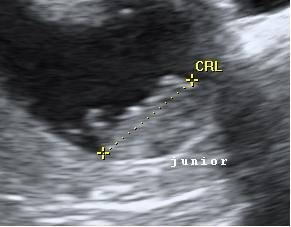

Så har vi igen været til scanning, og dte var bare en fantisk oplevelse, der var sket så meget på 2 uger, og den bette er vokset fint som den skal, der var både hjerteblink og hjertelyd, og endda lidt bevægelse, så det var bare helt perfekt, og enormt rørende

Ser nu frem til nakkefoldsscanning, og venter spændt på brev om hvornår vi skal derind